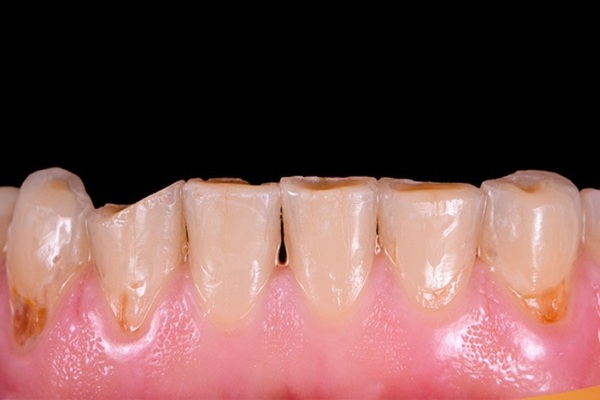

Bề mặt răng mòn, lộ lớp ngà vàng

Khi men răng bị mòn đi, lớp ngà màu vàng bên trong sẽ lộ ra, khiến răng trông xỉn màu, thô và kém mịn hơn. Vì ngà mềm và nhạy cảm hơn men, răng dễ bị kích thích khi gặp đồ ăn nóng, lạnh hoặc có axit. Tình trạng này không chỉ ảnh hưởng đến thẩm mỹ, đặc biệt ở răng cửa, mà còn gây ê buốt khi ăn uống.

Để cải thiện, bạn cần chăm sóc răng đúng cách, tránh các tác nhân gây mòn men và dùng các sản phẩm giúp bảo vệ men răng. Trong trường hợp cần thiết, trám hoặc bọc sứ sẽ giúp phục hồi bề mặt răng và giữ cho hàm răng luôn khỏe đẹp. Các phương pháp này hỗ trợ bảo vệ ngà răng, giúp duy trì sức khỏe răng miệng lâu dài.

Răng trở nên nhạy cảm khi chạm vào

Khi men răng bị mòn hoặc tổn thương, răng sẽ trở nên nhạy cảm hơn với nhiệt độ nóng – lạnh, thức ăn chua hoặc thậm chí gió lạnh. Người bệnh thường cảm thấy ê buốt, đau nhói như bị châm khi ăn uống. Điều này xảy ra vì lớp men không còn bảo vệ tốt, khiến lớp ngà và các ống dẫn truyền cảm giác bên trong bị lộ ra.

Để giảm tình trạng này, bạn có thể dùng kem đánh răng chống ê buốt hoặc các sản phẩm chứa nano hydroxyapatite giúp làm dịu và tái khoáng men răng. Nếu triệu chứng kéo dài hoặc ngày càng nặng, cần đến nha sĩ để kiểm tra và có phương án điều trị phù hợp, giúp bảo vệ răng lâu dài.